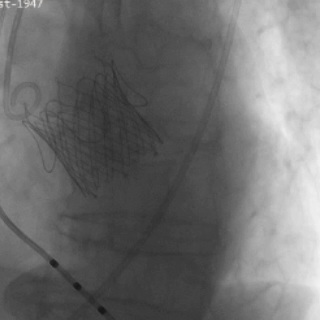

截止目前,臨床試驗進展順利,入組已接近尾聲。中期分析顯示手術成功率和安全性指標均符合預期標準。

瓣膜功能、形態良好,未見反流